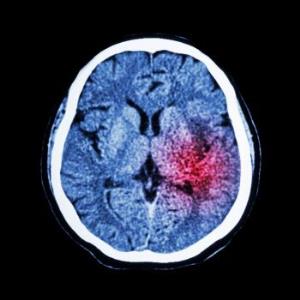

Избыточный вес и ожирение связаны с развитием нарушения кровоснабжения мозга. Однако новое исследование показывает, что лишние килограммы по-разному влияют на некоторые виды инсульта.

При прекращении кровоснабжения части мозга начинают умирать. Долгосрочные последствия инсульта зависят от того, насколько большой была площадь повреждения.

- Ишемический инсульт (инфаркт мозга) встречается в 87% случаев. Он возникает при прекращении кровоснабжения мозга, вызванного закупоркой сосуда.

- Геморрагический инсульт. Наступает при кровоизлиянии в мозг, причиной которого в большинстве случаев является высокое кровяное давление.

- Транзиторная ишемическая атака или микроинсульт возникает при временной закупорке сосуда. Ее обычно воспринимают как предупреждающий знак.